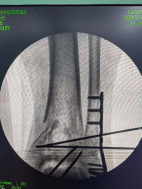

外側(cè)切口放置鋼板,固定腓骨。

穿針輔助復位脛骨遠端骨折塊,安裝內(nèi)固定